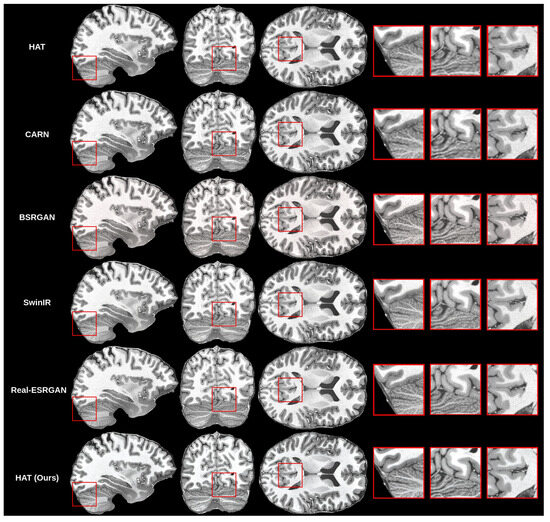

4.3. Results

4.4. Discussion